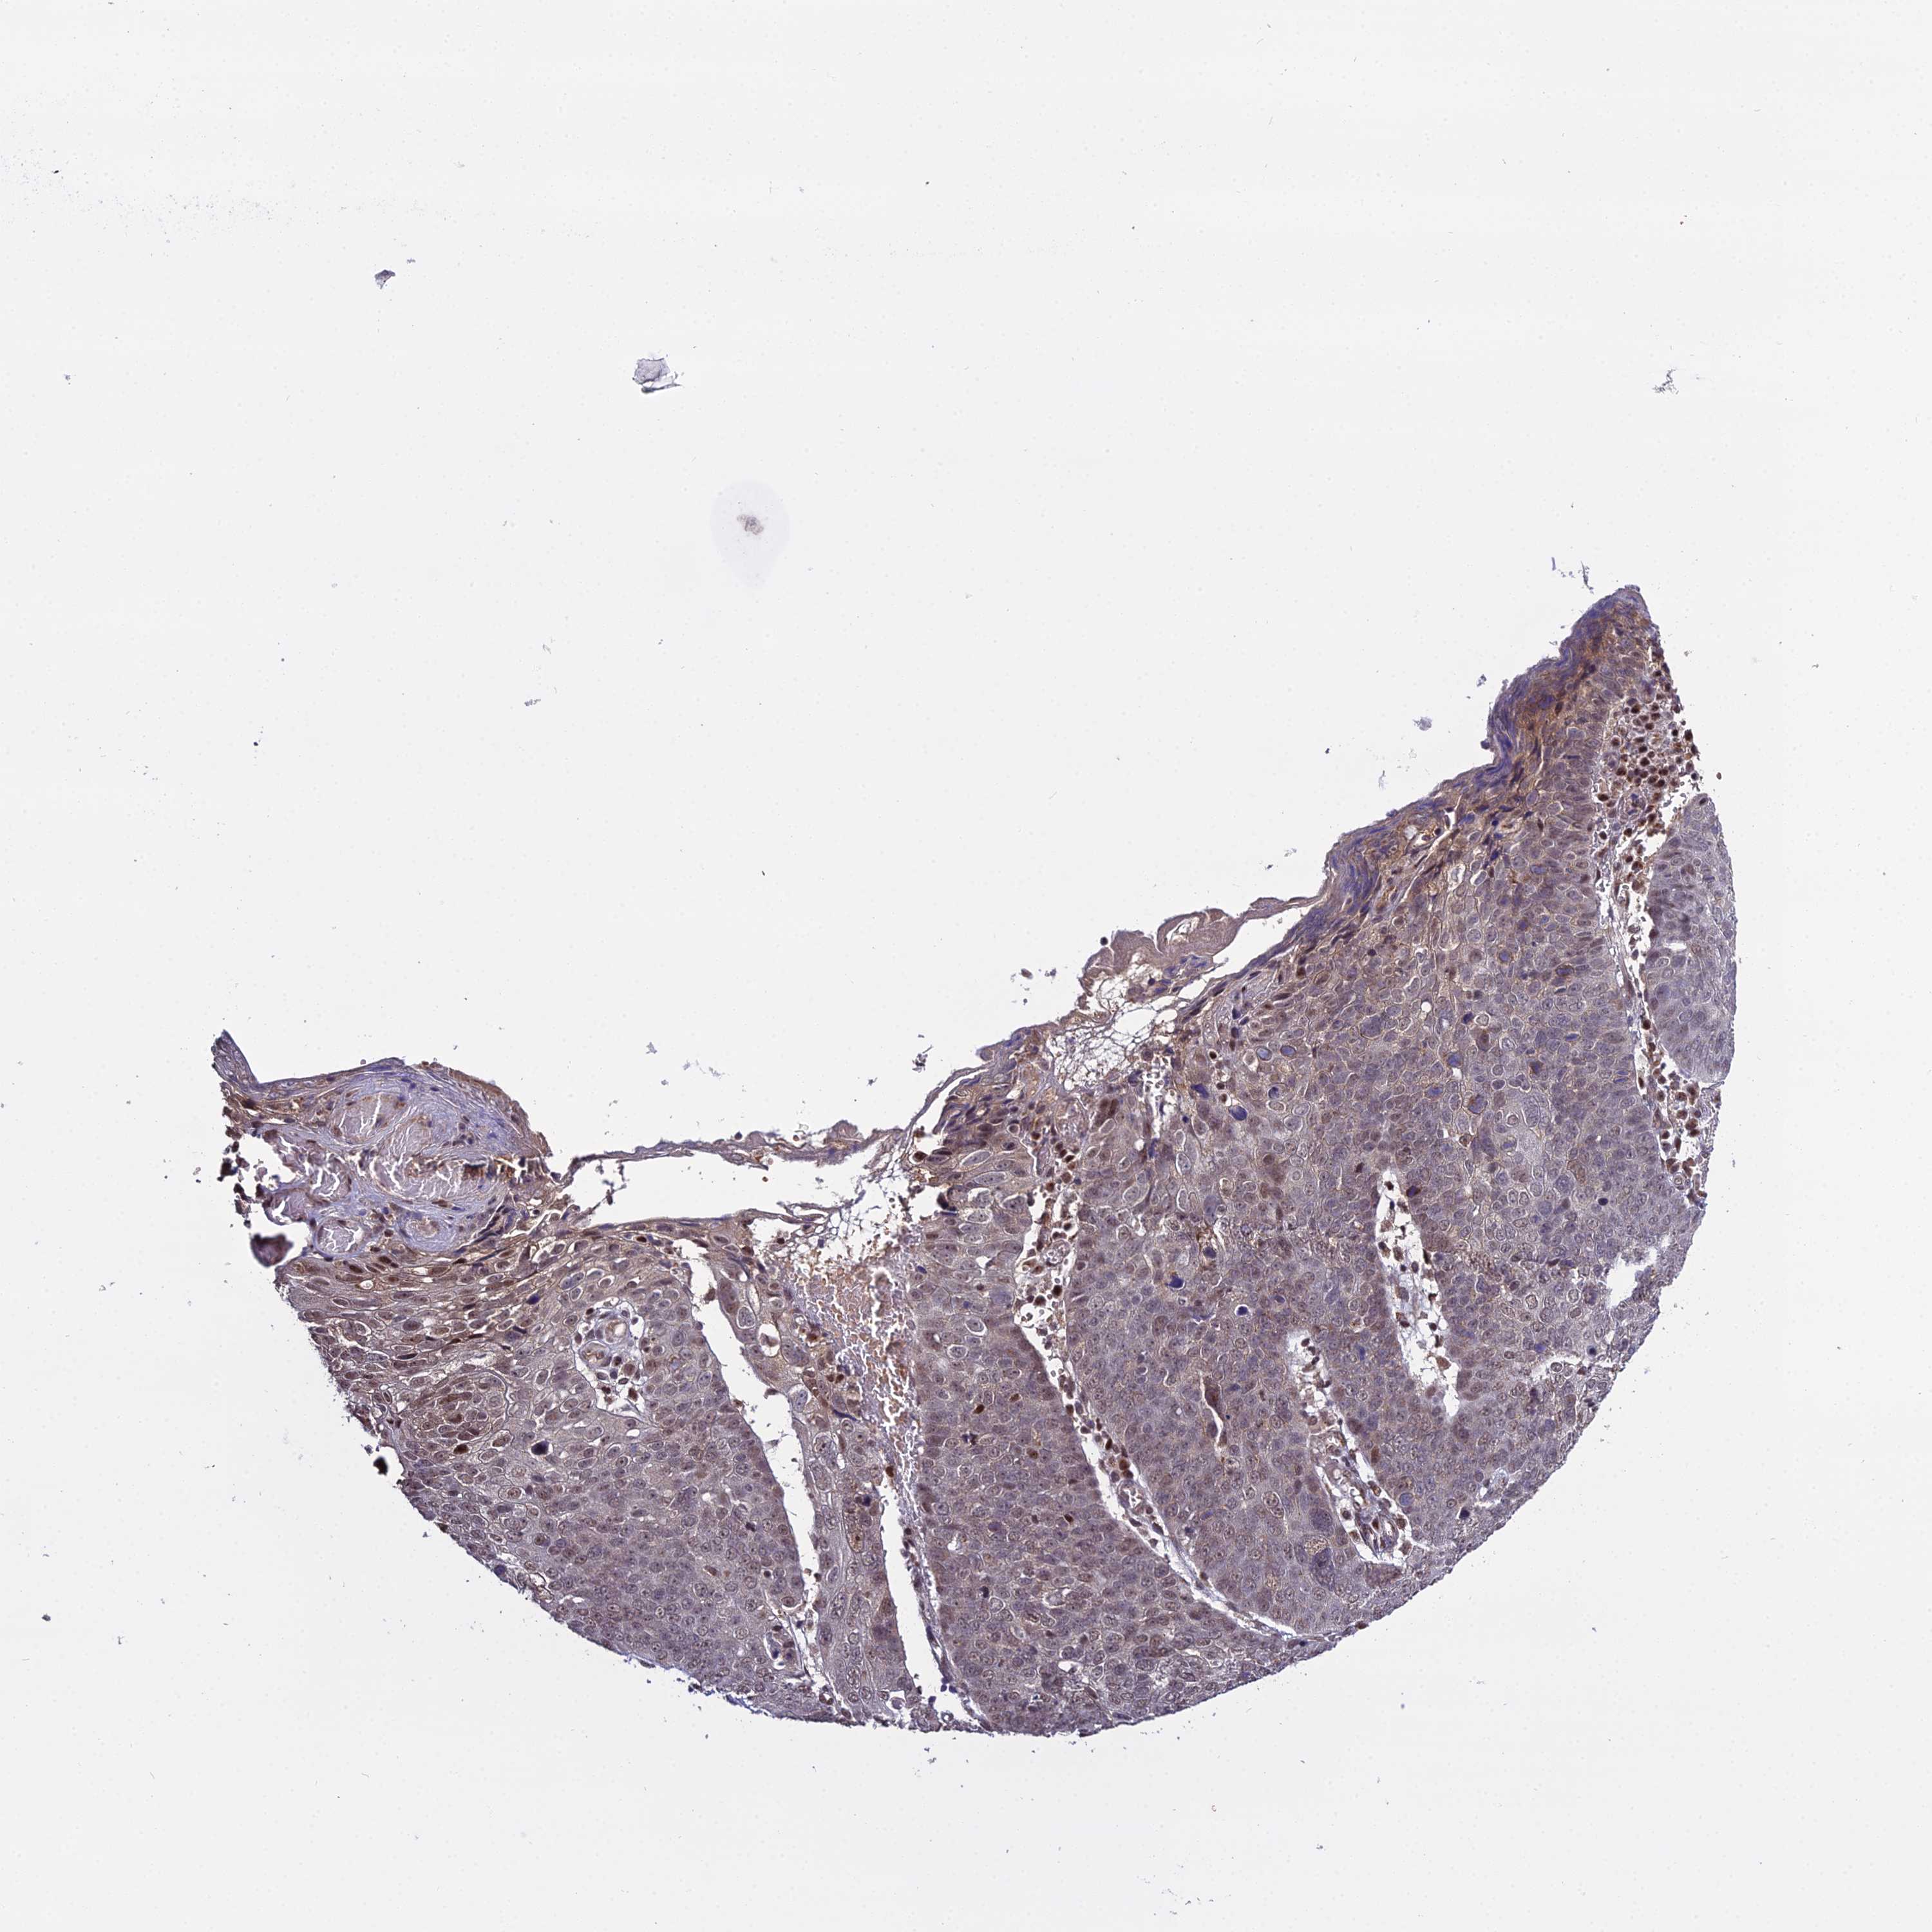

Basal cell and squamous cell cancer

SKIN CANCER - Protein expressioni

A mouse-over function shows sample information and annotation data. Click on an image to view it in a full screen mode. Samples can be filtered based on level of antibody staining by selecting one or several of the following categories: high, medium, low and not detected. The assay and annotation is described here.

Each image is clickable and will lead to virtual microscopy that enables deeper exploration of all samples and also displays staining intensity scores, fraction scores and subcellular localization as well as patient and tissue information for each sample.

Antibody HPA044610

Staining

High

Medium

Low

Not detected

Intensity

Strong

Moderate

Weak

Negative

Quantity

>75%

75%-25%

<25%

None

Location

Nuclear

Cytoplasmic/membranous

Cytoplasmic/membranous,nuclear

Squamous cell carcinoma, NOS

Squamous cell carcinoma, metastatic, NOS